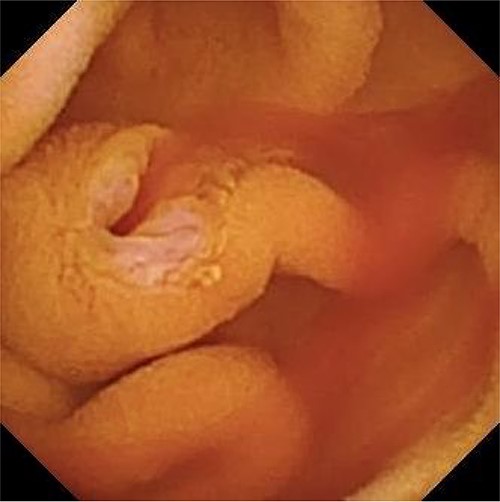

An 80-year-old male patient presented to his primary care physician with a chief complaint of fatigue. Further work-up was notable for IDA (Table 1). He was referred to a gastroenterologist and underwent an upper endoscopy that demonstrated some nodularity in the duodenum with evidence of mucosal changes of celiac disease, but final biopsy showed no suspicious findings. The colonoscopy was unremarkable. A capsule endoscopy was then performed which demonstrated fresh blood from an otherwise normal appearing ampulla of Vater, suggestive of a hepato-pancreatico-biliary source of hemobilia (Fig. 1). A follow-up computer tomography (CT) enterography demonstrated an abnormal appearing gallbladder with linear calcifications and intraluminal debris. The patient was subsequently referred to a surgical oncologist for hemobilia and an abnormal appearing gallbladder.

Capsule endoscopy showing fresh blood from an otherwise normal appearing ampulla of Vater.